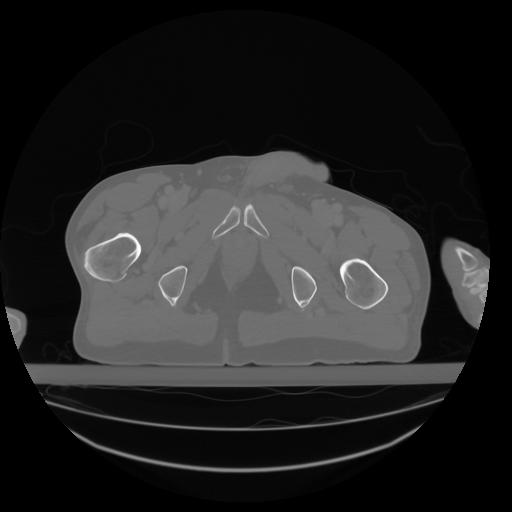

27 CUERPO,CE,Axial,3.0,CUERPO,,